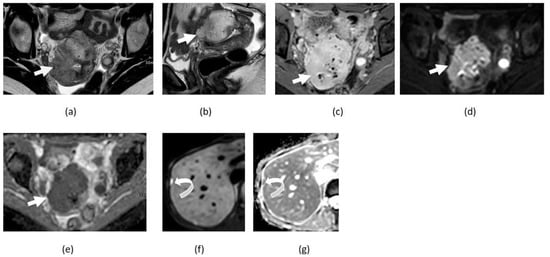

3.5. Mature Cystic Teratoma

3.6. Ovarian Fibroma, Fibrothecoma, and Thecoma

4. Clinical Applications in Gynecological Malignancies

4.3. Ovarian Cancer

5. Pitfalls of DWI